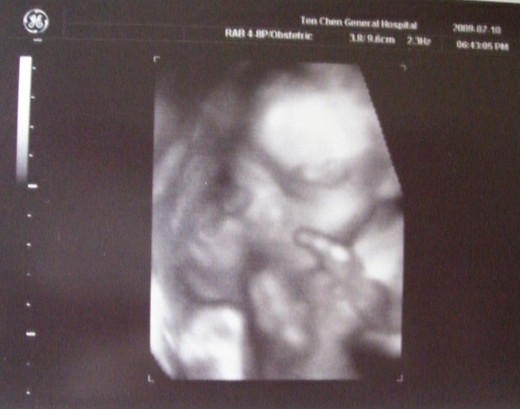

第一張照片是寶寶的側面..醫生說沒兔唇

第二張是4D的黑白照..被老公嫌扁鼻子(大概像我吧)